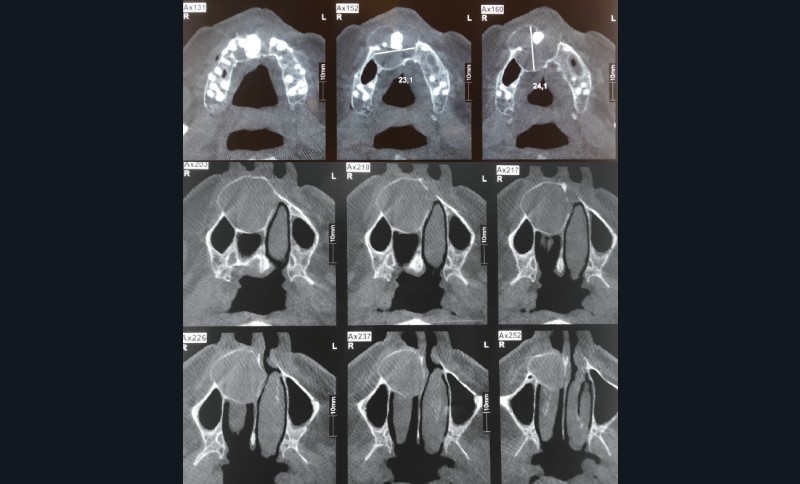

1. La panoramique (fig. 1) montre « une image » maxillaire antérieure. Il s’agit :

a. d’une image radioclaire maxillaire

b. d’une image radio-opaque maxillaire

c. d’un polype du sinus maxillaire droit

d. d’une dent incluse